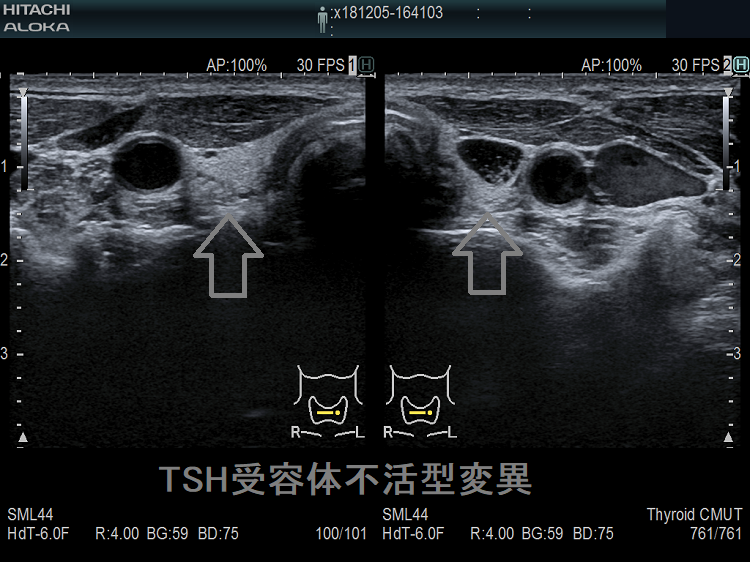

TSH受容体不活型変異は、TSH受容体(TSHR)遺伝子の異常で、遺伝性甲状腺機能低下症の1%を占めます。甲状腺ホルモン合成障害と同じく、両方の染色体に異常があるホモ接合型は重症甲状腺機能低下症として、新生児マススクリーニング(NBS)で見つかります。片方の染色体に異常があるヘテロ接合型は軽症甲状腺機能低下症なため、新生児マススクリーニング(NBS)で見つからず、幼児~成人発症になります(J Clin Endocrinol Metab. 2009 Apr;94(4):1317-23.)。

当然、橋本病の抗体陰性、エコー上、破壊性変化に乏しく、萎縮性甲状腺炎と同じに見えますが、TRAb(TSHレセプター抗体/TSBAb(TSHレセプター抗体[阻害型]、甲状腺刺激阻害抗体)は陰性なので鑑別できます。

R450H(p.Arg450His)は、日本人のTSH受容体不活型変異で高頻度に認められる遺伝子変異です(Thyroid. 2001 Jun;11(6):551-9.)。(第54回 日本甲状腺学会 O-3-1 新生児マススクリーニングで異常の認められなかった非自己免疫性甲状腺機能低下症の一兄弟例)